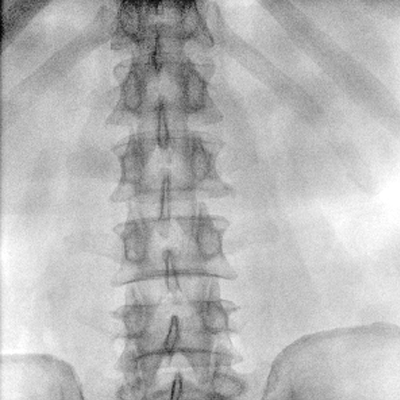

临床适用科室:骨科、普通外科、矫形外科、创伤外科、泌尿外科、脊柱外科、疼痛外科、消化科、妇科等科室。

大尺寸动态平板探测器,高DQE、低噪声、图像清晰。采用多分辨率图像增强处理技术,不同部位不同图像处理算法,满足客户多样化的需求。

采用智能变频脉冲透视技术,优化图像质量的同时降低辐射剂量,呵护医患健康